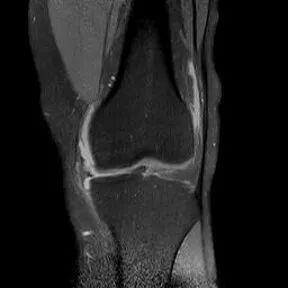

桶柄状撕裂MRI表现

1、宽度减小,在通过半月板体部的冠状面上蝶形消失,同时可见内移的半月板位于髁间窝、交叉韧带旁2、矢状面示残余的前角或后角变小或截断3、半月板前(后)角增宽或双半月板前(后)角征4、双前交叉韧带或双后交叉韧带征

半月板撕裂:桶柄状撕裂(双前角征)